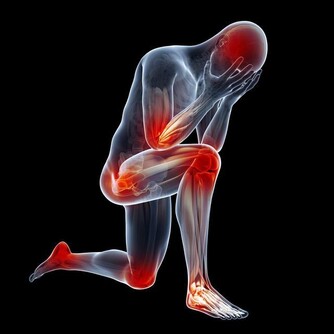

對絕食並且死亡的人進行檢查後,揭示了以下可能的死亡原因:

多器官衰竭;

心室顫動或快速心律,導致心臟泵血作用不佳,並可能導致意識喪失甚至死亡;

嚴重膿毒症(血液中毒),身體因感染而傷害自己的器官和組織。